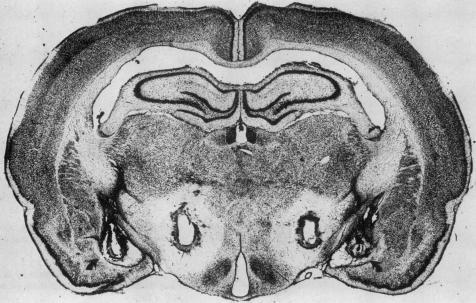

进食行为的启动和终止尚未完全明确。胃被认为是调节食物摄入信号的一个来源。食物的视觉和嗅觉是胃酸分泌和胃收缩的有力刺激因素。口腔、上消化道和肝脏含有调节食物摄入的受体;传入信息传入脑干和脑区。下丘脑外侧损伤会导致进食停止、体温升高、基础胃酸分泌增加,并产生胃糜烂。迷走神经切断术和给予溴丙胺太林可消除此类损伤后胃酸分泌的增加;它们还会改变黏膜屏障,使质子扩散到黏膜细胞中。几种神经肽通过中枢神经系统,通过调节自主神经系统来刺激或抑制胃酸分泌。大多数胃糜烂的动物模型都与体温降低有关。尚不清楚这种关联是否是促甲状腺激素释放激素水平升高的结果,当脑池内注射促甲状腺激素释放激素时,它是胃酸分泌和糜烂形成的有力刺激因素。

https://cdn.ncbi.nlm.nih.gov/pmc/blobs/d394/1306273/9ff8623dd1c8/westjmed00168-0074-a.jpg